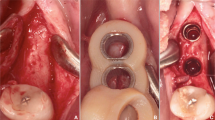

Three 2.4-mm screws were placed to demarcate the anterior midline and posterior lateral lines on each side of the model. Computer-aided design/computer-aided manufacturing (CAD-CAM) wax (MarmoScan; Siladent, Goslar, Germany) was used to cover the screw heads and facilitate recognition during optical scanning (Fig. 2). We utilized a high-resolution cone-beam computed tomography machine (Planmeca Promax 3D Mid Dental Volumetric Tomography, Helsinki, Finland) to perform the CBCT scans. These scans were carried out using the subsequent parameters: 90 kV, 10 mA, and 36 s, with a Field of View (FOV) of 16 × 9 cm. White CAD-CAM spray (Dr. Mat, Istanbul, Turkey) was applied to the models to obtain higher-quality scans. The scanned gingival surface texture was transferred to the software of the NeWay optical 3D scanner (Open Technologies, Rezzato, Italy) (Fig. 3).

coDiagnostiX software (Dental Wings Inc., Montreal, Canada) was used for implant planning and designing surgical guides. The radiopaque, wax-covered screw heads were used for accurate superposition of the STL and DICOM data. The gingival thickness of 3 mm on all surfaces and the cortical outer surface of 4 mm were measured and double-checked again on software, and models that did not have these features were not included in the study. After segmentation and marking of anatomical landmarks, virtual implants were positioned considering the available bone volume. Straumann (Basel, Switzerland) bone-level tapered implants (3.3 mm × 12 mm) were used in all regions. Four implants (two axial and two tilted) were planned for all models. In the mandibular models, the axial implants were located close to teeth #32 and #42. Two posteriorly angulated implants were positioned in front of the mental foramen at an approximately 30° angle. In the maxillary models, the axial implants were located close to teeth #12 and #22. Posterior angulated implants were placed in front of the anterior maxillary sinus wall at an approximately 30° angle. A constant anterior–posterior distance was maintained between the virtual implants. The surgical guide was designed using a sleeve of 5.0 mm in diameter and height. The guide design was sent to the laboratory and printed using the CARES P30 printer (Straumann). The entire process, from implant planning to surgical guide design, was overseen by a Straumann digital product consultant (Fig. 4).